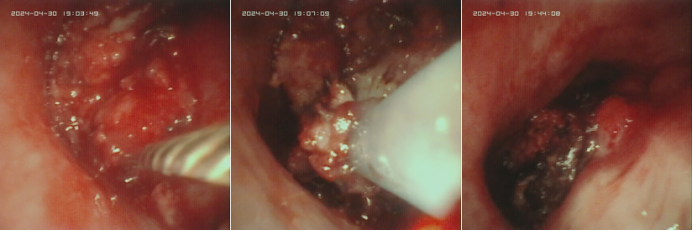

病例459岁男性患者,因“确诊右肺肝样腺癌2月余,气促2天”入院诊断:右肺肝样腺癌并双侧肺门及纵隔多发淋巴结转移住院第3天突发大咯血窒息。紧急插管予呼吸机支持后,床边纤支镜发现气管下段、右主支气管血凝块堵塞,右中、下肺新生物及血凝块导致管腔狭窄(图7)。予纤支镜下药物治疗+射频消融术+钳检等综合介入处理,历经约5小时抢救后生命体征稳定,转介入室行支气管动脉栓塞术,最终成功控制出血,患者病情逐步稳定。

图片

6  患者胸部CT

7  镜下见血凝块及新生物堵塞